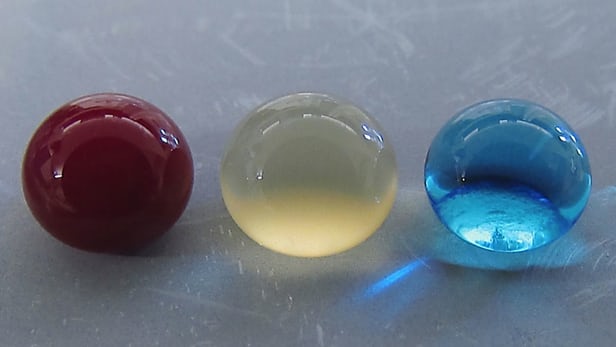

具體來說, 科學家Arun Kota和Ketul Popat 在鈦片上培養了一種超級疏血(superhemophobic – blood)的「表面」。研究人員在實驗室測試中對不同類型的「表面」進行了測試, 並發現氟化納米管的表面紋理和化學性質能產生最低水準的血小板粘附。